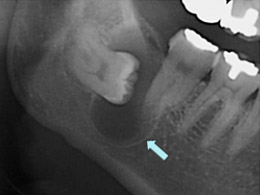

場合によっては、定期的な健康診断で医師が濾胞性嚢胞があることを知ることがあります。あなたが出産可能な年齢で、それ以外は健康で、何の症状も示さない場合、医師は嚢胞が自然に解決するまで放置する可能性があります。定期検査の際にそれが成長していないことを確認するために監視する場合があります。場合によっては、膣超音波検査やその他の検査も推奨される場合があります。

下腹部の痛みやその他の症状がある場合、医師は原因を診断するために内診を行うことがあります。症状や病歴に応じて、超音波検査、CT スキャン、MRI スキャン、その他の検査も推奨される場合があります。医師が正確な診断を下すことが重要です。破裂した嚢胞の症状は、多くの場合、虫垂炎や他のいくつかの病気の症状と似ています。